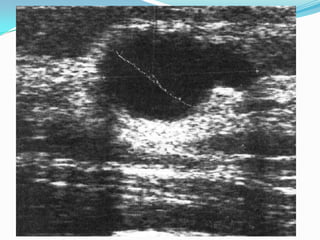

GALACTOCELEQUISTE MAMARIO  DE CONTENIDO LACTEONO HAY SIGNOS DE INFLAMACION O ABSCEDACION EN SU INICIOLAS MEDIDAS COMO CALOR MASAJE  LACTACION

GALACTOCELE